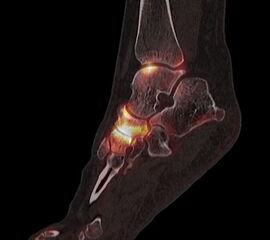

Die Kombination von SPECT und CT in einem Untersuchungsgang bringt wie bereits oben erwähnt eine erhöhte Ortsauflösung und artefaktfreie Darstellung von Knochenstoffwechselveränderungen der SPECT bei gleichzeitig excellent guter anatomischer Darstellung/Zuordnung durch die CT 3. Auf die Vorteile der CT gegenüber dem konventionellen Röntgen muss nicht mehr besonders eingegangen werden. Besonders eignet sich die „SPECT-CT“ zur Diagnostik von Fußerkrankungen (Biersack HJ et al. 2012).

Aufgrund der optimalen funktionellen Darstellung (PET) und der entsprechend guten anatomischen Bildgebung kann dieses kombinierte Untersuchungsverfahren viele Fragestellungen auch im Bereich des Fußes beantworten. Exemplarisch werden folgende Indikationen erwähnt. Abklärung von Infektionen im muskuloskelettalen Bereich 45, Untersuchungen von unklaren Fußschmerzen (Biersack HJ et al. 2012), präoperative Bildgebung beim Charcot-Fuß/diabetischer Fuß 31.